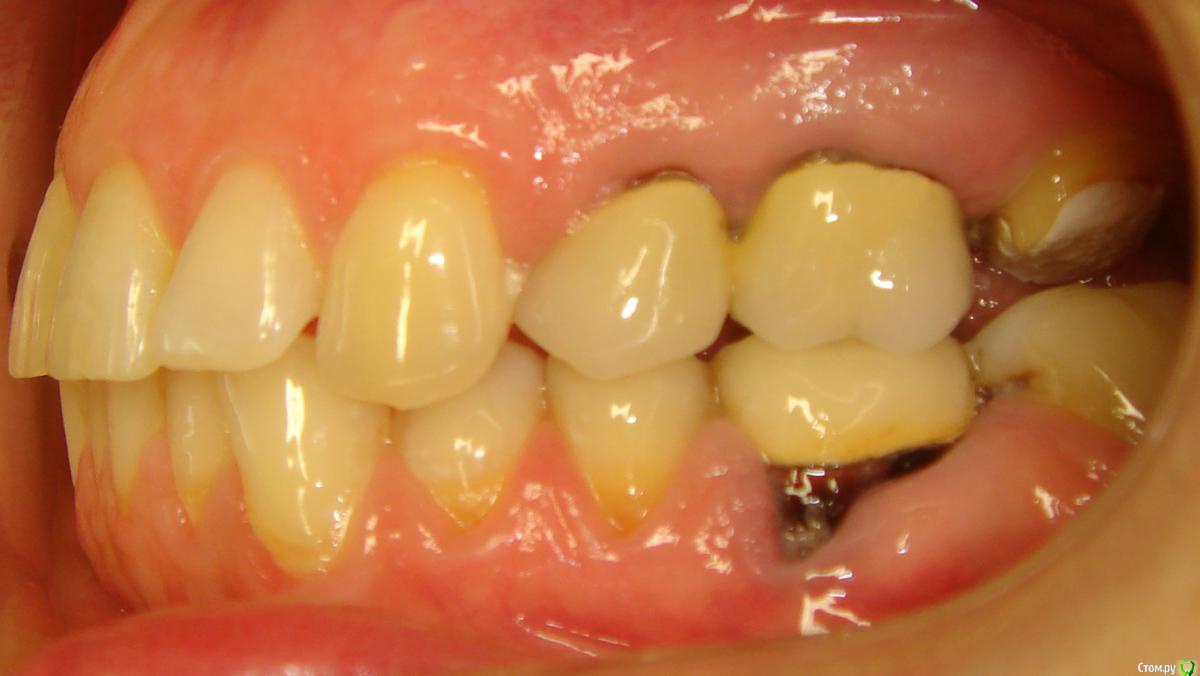

Opdihatop Опубликовано 16 апреля, 2017 Поделиться Опубликовано 16 апреля, 2017 Здравствуйте, коллеги! Что вы думаете по поводу этого случая? Объективно: вертикальный рост, первый костный класс. Незначительная протрузия резцов в/ч, нормальный наклон резцов н/ч. 15 зуб ретенирован. Значительное сужение в/ч, сужение н/ч.Вопросов 2: 1) Тянуть ли 15 зуб? 2) Планирую расширять при помощи SARPE, что делать с образовавшимся местом (которое и так сейчас уже есть)? Мне кажется такие большие реставрации будут некрасивыми. Ссылка на комментарий

Brigita Опубликовано 16 апреля, 2017 Поделиться Опубликовано 16 апреля, 2017 (изменено) Здравствуйте, коллеги! Что вы думаете по поводу этого случая? Объективно: вертикальный рост, первый костный класс. Незначительная протрузия резцов в/ч, нормальный наклон резцов н/ч. 15 зуб ретенирован. Значительное сужение в/ч, сужение н/ч.Вопросов 2: 1) Тянуть ли 15 зуб? 2) Планирую расширять при помощи SARPE, что делать с образовавшимся местом (которое и так сейчас уже есть)? Мне кажется такие большие реставрации будут некрасивыми.1) а куда его?2)Реставрации передних зубов имеется ввиду? Не такой большой промежуток, можно и реставрацию, если виниры не может позволить. расширение на SARPE - в таком возрасте без хирургии маловероятно, Вы же сами знаете, получите зубоальвеолярное небольшое расширение и наклон. Такой тонкий биотип, что там еще с кортикалкой будет. Мосты спаянные, вкладки. Чтобы узнать положение 5го надо КТ сделать, где у него корень - пойдет ли. Он видимо в небной костиА вообще - отдайте ее ортопедам. Она сама то что хочет? Изменено 16 апреля, 2017 пользователем Brigita Ссылка на комментарий

Brigita Опубликовано 16 апреля, 2017 Поделиться Опубликовано 16 апреля, 2017 Черные треугольники заполнить и рецессии убрать. я вот чего то не понимаю наверно.. где треугольники, которые она хочет убрать? я вижу диастему, трему 22-21, кариес 11-12, многочисленные рецессии, плохие ортопедические коронки, неправильно выполненные вкладки ( а может правильно? я не ортопед), скученность нижних зубов. А вообще вот интересно - в каком возрасте максимально возможно расширение на SARPE, у кого какой опыт? Ссылка на комментарий